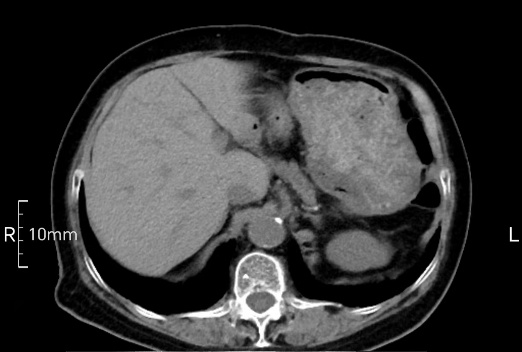

完美禁食且喝飽飽,胃壁完美展現。